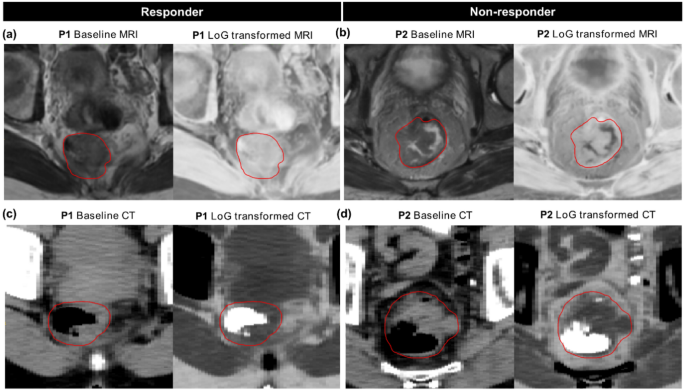

The clinical model containing only cT stage achieved training and validation AUCs of 0.60. Combining cT stage with the combined signature from MRI and CT achieved the best validation result with an AUC of 0.70. At a threshold of 0.248 this signature was able to accurately classify 16/21 responders and 20/47 non-responders (Supplementary Fig. S3). Figure 2 shows receiver operating characteristic (ROC) curves and the corresponding calibration plots for this signature on training and validation data. All features represented independent information (Supplementary Fig. S4) and significantly contributed to the prediction in training (p < 0.05), while only MR_log_stat_min was significant in validation (p = 0.04). The MRI feature log_stat_min (IBSI:1GSF) represents the minimum intensity, while the CT feature log_ih_max_grad_fbn_n32 (IBSI:12CE) represents the gradient of the discretised histogram (32 bins) within the GTV on the LoG transformed image. Image-based interpretation of these features is presented in Fig. 3. In the non-responder group, MR_log_stat_min showed relatively low values, which translates to the existence of bright voxels in the GTV on the original baseline T2w MRI (Fig. 3b). In comparison, responders showed no such high grey values (Fig. 3a). Box plots of these features (Yeo-Johnson transformed and z-score normalized) in the two response groups are shown in Supplementary Fig. S5.

Representative images from MRI (a,b) and CT (c,d) with corresponding Laplacian of Gaussian (LoG) transformed images from two patients (P) in the two response groups, i.e. responder: P1 and non-responder: P2 on the training data. Red contours mark the gross tumour volume (GTV). P1 (responder: TRG = 4) showed an overall homogenous appearance on the baseline MRI. On the contrary, P2 (non-responder: TRG = 1) showed a more heterogeneous GTV with a low stat_min value on the LoG transformed MR image, which corresponds to some high pixel intensities on the baseline MRI. Similarly, a more homogenous GTV (excluding the air voxels) can be seen in P1 compared to P2 on the baseline and LoG transformed CT slices, possibly causing low gradients in the intensity histogram for the responder.